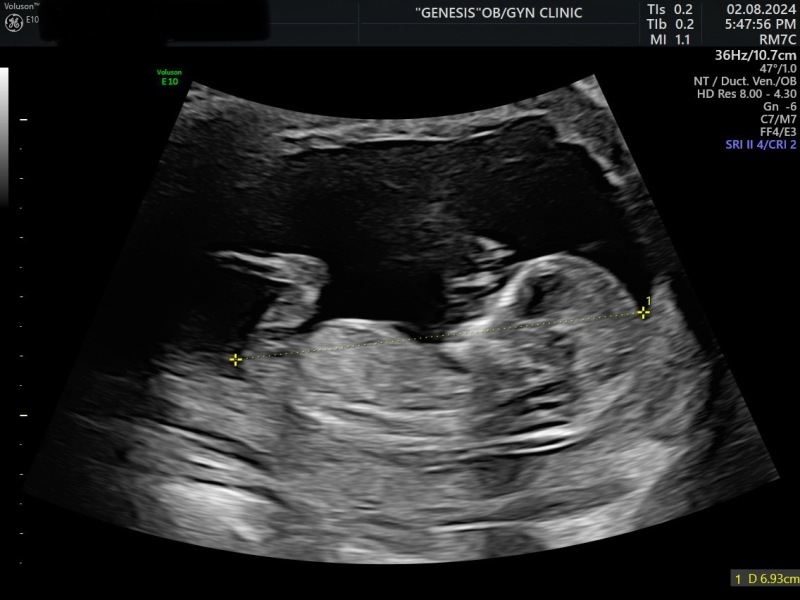

Felicity20 · 04/08/2024 09:28

Hello, got boy based on nub theory on week 12, is there a chance to have a girl? Has anyone such an experience? Thanks in advance!

Has anyone had nub theory be wrong?